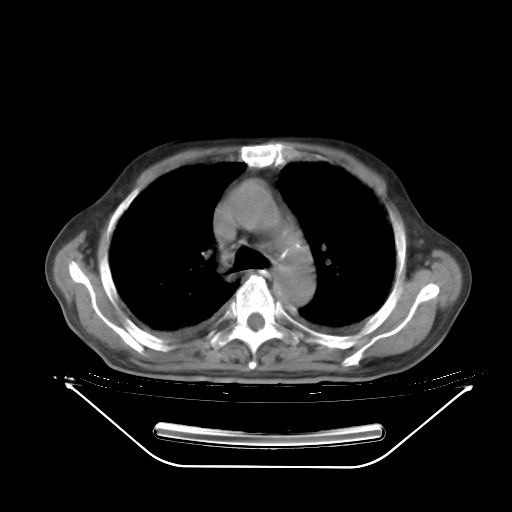

今天复查肺部CT,发现双肺广泛磨玻璃样改变。所以我把3月19日和5月9日相隔50天的肺部CT上传。请大家会诊。

2009年3月19日肺部CT片。

2009年3月19日肺部CT